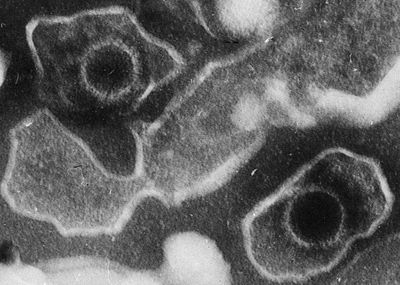

Ученые показали нуклеазную функцию необходимого вирусу Эпштейна — Барр белка

Это открывает путь к разработке новой группы лекарственных средств